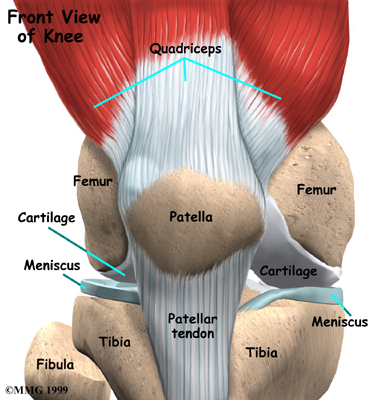

Please annotate this diagram with the site(s) of swelling or tenderness.

Right Knee

Notes: -

Left Knee

Notes:-